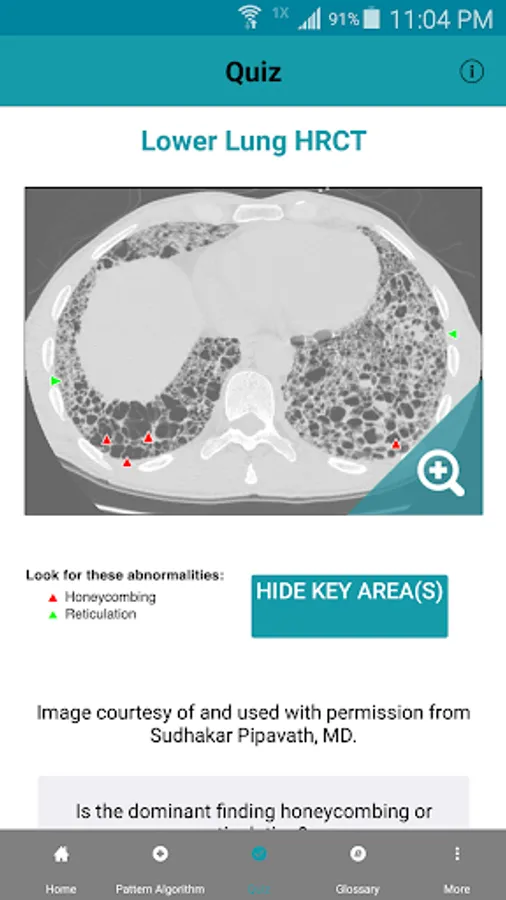

Rad Rounds - UIP to IPF is an innovative, peer-reviewed resource that provides practicing and future pulmonologists and radiologists with training and references for recognizing and evaluating usual interstitial pneumonia (UIP) and interstitial lung diseases (ILDs) on high resolution computed tomography (HRCT). Through this application the user can access learning materials such as a step-by-step pattern recognition algorithm, utilizing user-provided HRCT scans, an interactive UIP/ILD glossary and image gallery to further assist in the evaluative process, several “test your knowledge” quizzes, and a series of short informational videos, covering subjects such as: Basic HRCT Technique, Imaging Positions, and Recognizing Features of ILD on HRCT. This app is ideal for: radiologists that would like to use the interactive algorithm to help assess their HRCT scans, pulmonologists that want to evaluate their own cases or learn more about HRCT in the diagnosis of ILD, and medical students and residents that want to learn about HRCT and ILD. Download now and find out: Is It UIP?

Rad Rounds - UIP to IPF Screenshots